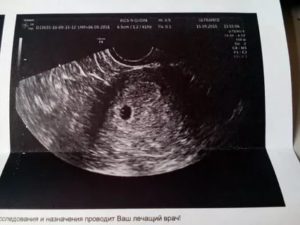

Сегодня ходила на повторное УЗИ, первое делала 10 дней назад, там увидели плодное яйцо 5 мм и сказали, что всё хорошо. Моя Г считает, что УЗИ не вредно, но очень информативно — я с ней согласилась, поэтому решено было сделать ещё одно УЗИ для контроля.

На втором УЗИ увидели уже бусинку внутри плодного яйца, увидели пульсацию сердца, но ещё увидели гипертонус матки. Г и врач УЗИ не стали меня сильно пугать, старались успокоить, но предупредили об угрозе выкидыша. Я уже более двух недель пью Магне B6 и обычный набор витаминов.